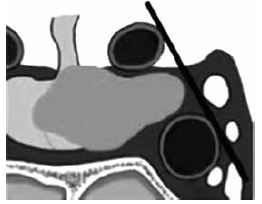

Observe a imagem.

Enunciado 2263449-1

Um macroadenoma que possui extensão lateral que termina entre a linha intercarotídea e a margem lateral do seio cavernoso é classificado como KNOSP: